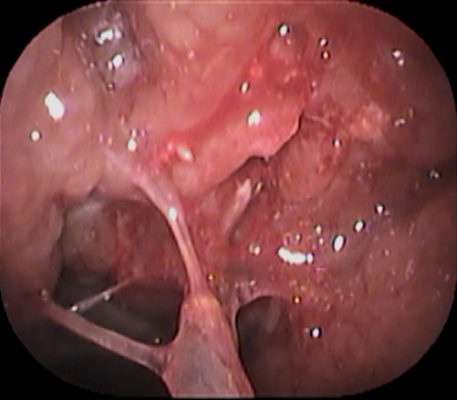

続いて、口👄からBスポット治療をおこないました。

こちらも かなり出血しました。

その後 しばらく通院し 何度かBスポット治療をおこない、症状は緩和されていきました。